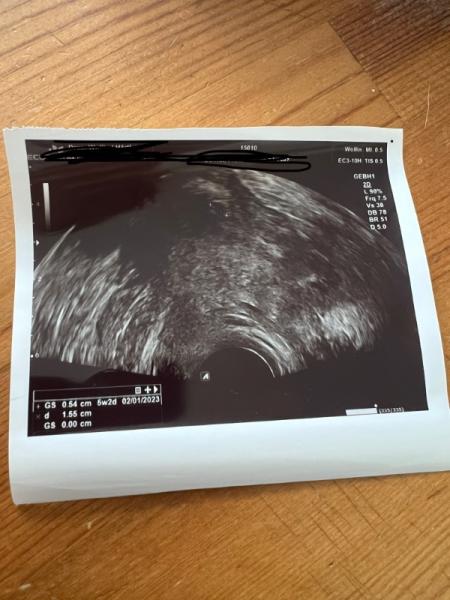

Fruchthöhle ja oder nein

Bild zu Fruchthöhle ja oder nein - Forum für Januar - Mamis

Ich dachte kurz, dass ich da zwei Fruchthöhlen sehe. Kann mich natürlich auch irren. Ich bin nicht gut in sowas

Das Problem ist ja ist sehe da überhaupt nix

Hallöle liebe Franzi, Mein Ultraschall sieht ähnlich aus und ich bin auch in der 5ssw. Es ist einfach noch zu früh !.:) Mach dir nicht so viele Sorgen. Ich habe kommenden Montag erneut einen Termin weil meine Ärztin ebenso wie bei dir keine Höhle sehen konnte bzw nur eine erahnen konnte. Wann musst du das nächste mal zum doc ?